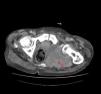

We report the case of an 82-year-old male patient diagnosed 10 years prior with Paget's disease and polyostotic involvement. Relevant history showed atrial fibrillation and chronic heart failure. He came to the immediate care clinic (UCAI) due to fatigue, anorexia and edema of the lower extremities, which had been present for 15 days. The systems review referred pain in the left ischiopubic region since 6 months before, which had been increasing and appeared both at rest and with exercise. He was admitted for heart failure treatment and study of the origin of pain. Physical examination showed pale skin and mucous membranes, irregular cardiac auscultation with systolic aortic murmur, decreased breath sounds on widespread lung auscultation, pitting edema up to the root of both lower limbs and pain on movement and decreased function of the left hip joint. On rectal examination there were no masses but only with remnants of normal stool. Complementary tests showed hemoglobin of 9.5g/dl with normal mean corpuscular volume and hemoglobin, CRP: 21.2mg/dl (0.2–0.8), fibrinogen: 722mg/dl (200–400), glomerular filtration rate: 120mm (1–15), alkaline phosphatase, 155U/l, iron: 23.6mg/dl (50–150) transferrin: 155mg/dl (300–360), ferritin: 1144mg/l (50–350), saturation index: 12% (20–40), soluble transferrin receptor: 7.88mg/l (2–4), tumor markers were normal. The chest X-ray showed bilateral pleural effusion and small lesions consistent with Paget's disease in both shoulders and the fifth left rib. Pelvic X-ray showed multiple lesions consistent with Paget's disease and a larger lytic image on the left ischium (Fig. 1). A bone scan was performed which showed images compatible with Paget's disease and no uptake in the left ischium (Fig. 2). A thoraco-abdominal CT-scan revealed a large pelvic mass with lobulated contours and foci of calcification that destroyed the left ischium and acetabulum measuring 12cm×12cm×16cm (Fig. 3). Suspecting a bone neoplasm added to Paget's disease the patient underwent an iliac bone biopsy which was consistent with undifferentiated pleomorphic high grade non osteogenic sarcoma, vimentin positive, with coexpression of CD-68 and low expression of actin and desmin. The patient outcome was unfavorable, suffering great malaise and difficulty controlling the pain, he decided to initiate treatment with radiotherapy for symptomatic control fundamentally. Finally, the patient died a week after the pathological diagnosis.